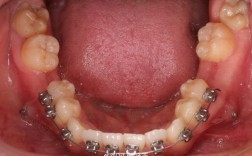

龅牙(上颌前突)通常由牙弓空间不足导致牙齿拥挤或前突,国际口腔正畸学会(WFO)2023年报告显示,约65%的龅牙病例需通过拔牙创造空间以实现理想排列,常见拔牙选择包括:

- 第一前磨牙:拔除后提供7-8mm间隙,利于前牙内收(占拔牙病例的72%)

- 第二前磨牙:适用于轻度拥挤病例(占18%)

随着隐形矫治技术进步,部分病例可通过以下方式避免拔牙:

- 邻面去釉(IPR):磨除牙齿间0.2-0.5mm釉质,美国正畸协会(AAO)2024年指南指出其适用性提升至43%的轻度拥挤病例

- 扩弓治疗:尤其适用于青少年患者,上颌扩张成功率可达81%(《Journal of Clinical Orthodontics》2023年数据)

- 推磨牙向后:配合种植支抗,单侧可获得3-5mm间隙